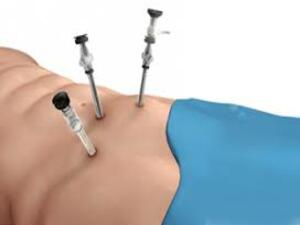

His special interests are in the field of Laparoscopic Hernia Surgery, Laparoscopic Upper G.I Surgery, Laparoscopy in Gastrointestinal Cancers and Bariatric Surgery. He is also actively involved in publications in peer – reviewed journals.